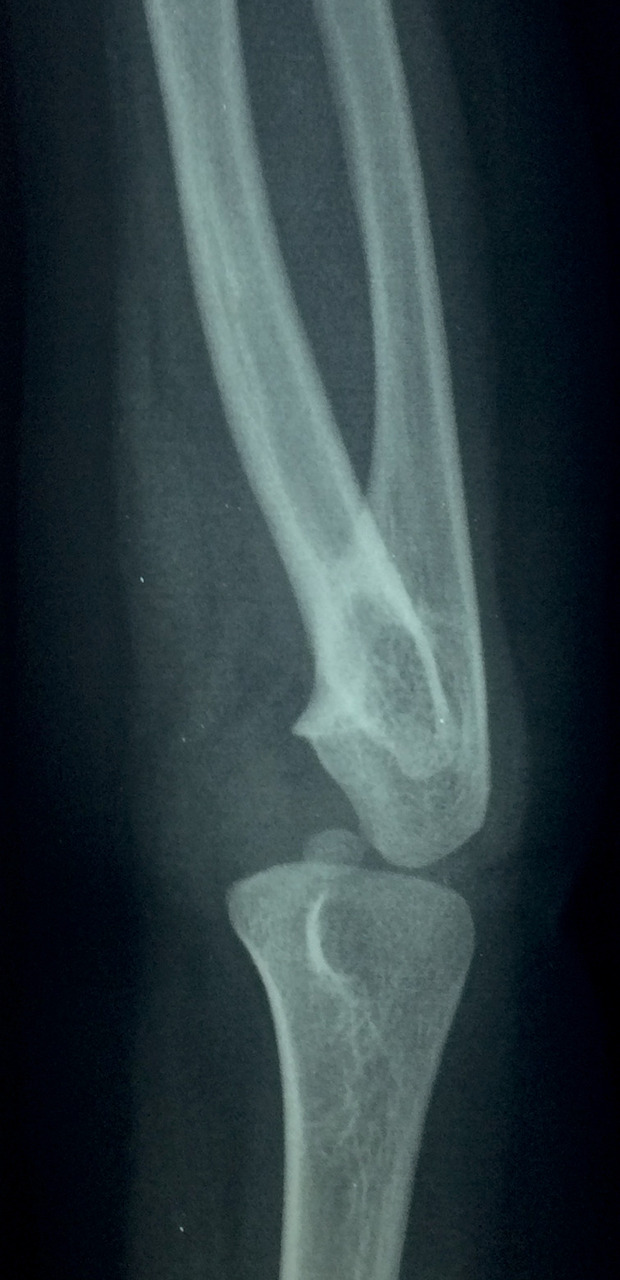

À la radiographie de l’avant-bras et du coude : fusion des parties proximales de radius et de l’ulna (fig. 1 et 2).